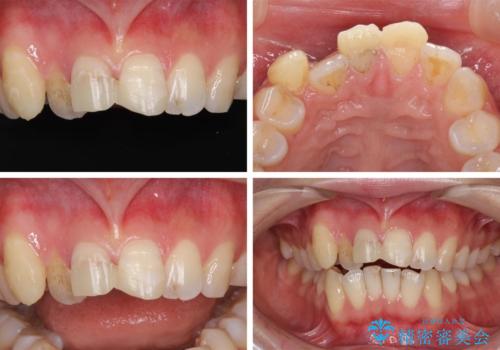

- 転倒により前歯の一部が欠けてしまったとのことで来院された患者様です。

神経が保存できる歯、神経を除去しなければならない歯、抜歯が必要な歯があり、ブリッジやインプラントなどによる治療を提案しました。

元々歯並びが気になっていたとのことで、前歯の治療を行うことを契機に矯正治療も行うこととしました。

本来であれば積極的に小臼歯を抜歯して口元を下げても良いのですが、前歯を1本抜歯しないといけなくなったため、非抜歯矯正をインビザラインを用いて行うこととしました。